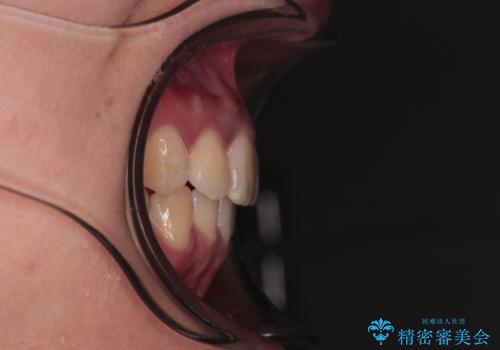

前歯のデコボコと隠れてしまう下顎前歯 インビザラインですっきりと改善

- 前歯のデコボコと、深い咬み合わせにより前歯が隠れていることを気にして来院された患者様です。